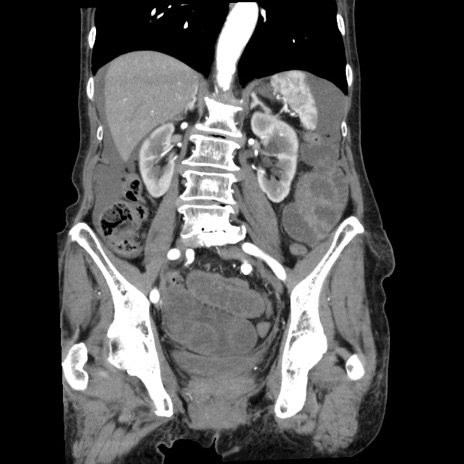

症例1(冠状断像)

【症例】80歳代女性

【主訴】腹痛

【現病歴】8時間前から腹痛あり来院。

【既往歴】糖尿病、脂質異常症、子宮体癌にて子宮全摘術

【身体所見】意識清明・会話良好だが腹痛で苦悶様、全腹部にわたって反跳痛と圧痛あり

【データ】WBC 13600、CRP 0.14、LDH 224、CK 90